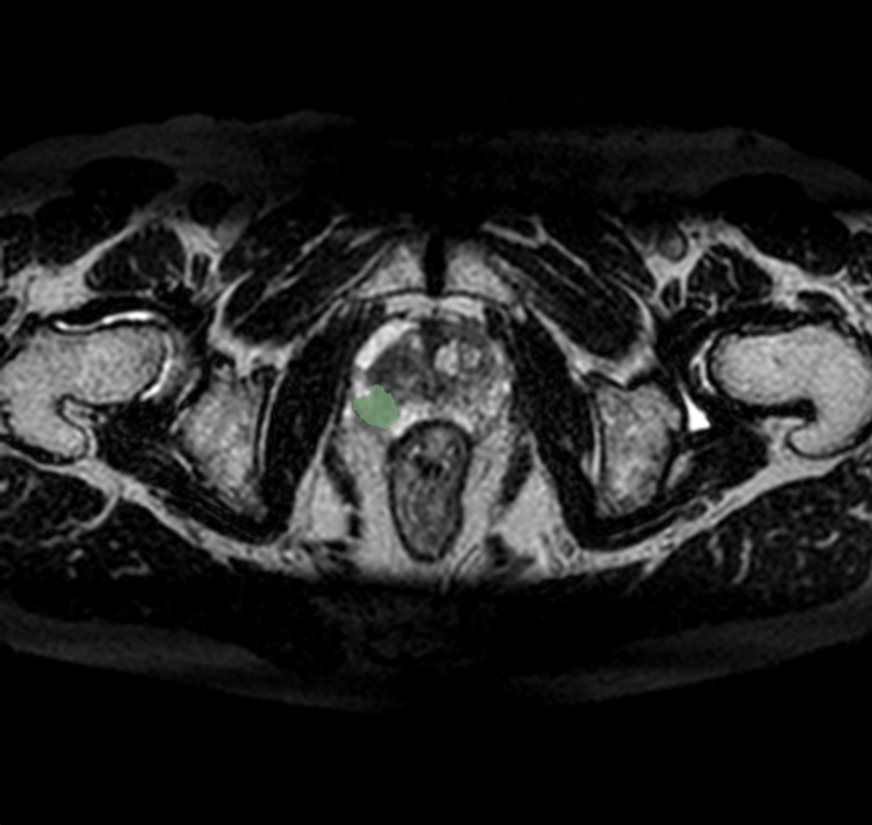

Callisto DataHub 2周年を記念し、専門医が作成した病変BBox付きの肺がん疑いX線データセット 50症例と、病変セグメンテーション付きの前立腺がんMRIデータセット(PI-RADS 4・5) 50症例を無料配布しています。前立腺がんMRIデータセットには、T1w, T2w, DWI, ADC, (あれば)DCEが含まれます。いずれも日本の医療施設由来で、所見文付き・商用利用可能なデータセットです。